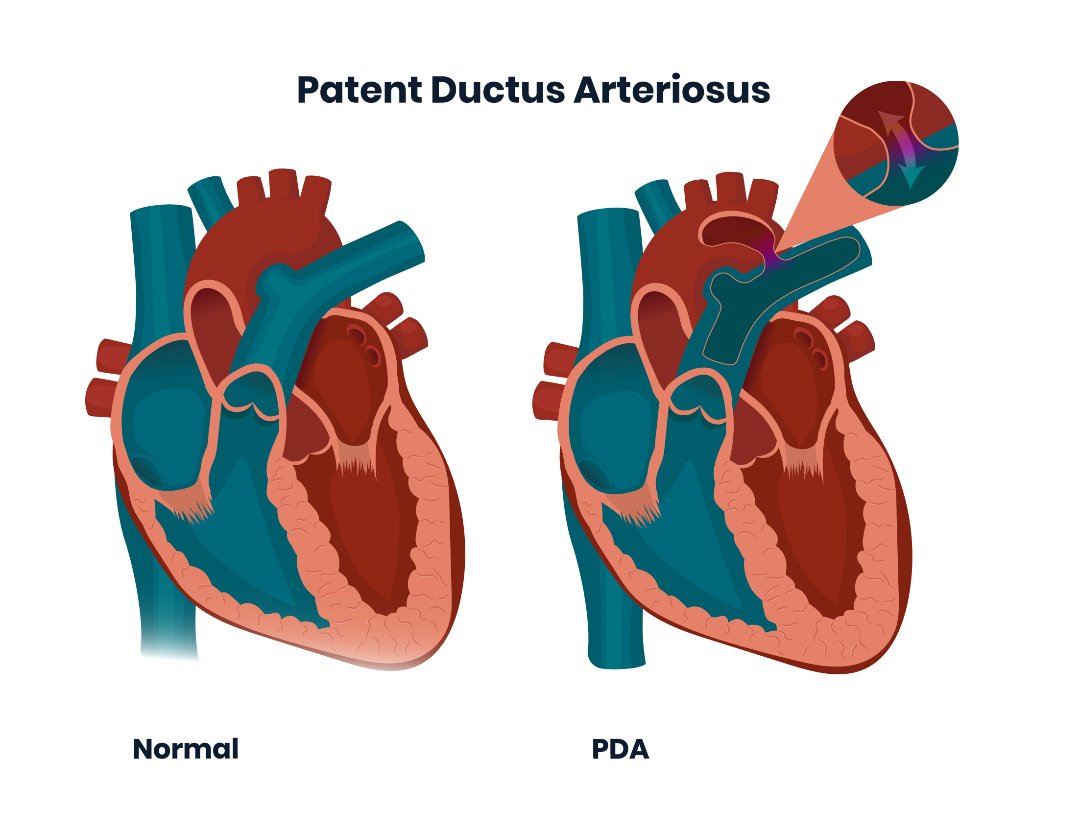

PDA Pathophysiology and Anatomy

Morphology of the PDA in premature infants The PDA resembles a hockey

What is this PDA and why do the doctors want to close it

Text Patent Ductus Arteriosus PDA in Premature Infants

PATENT DUCTUS ARTERIOSUS PDA IN CHILDREN Dr Gaurav Agrawal

What is PDA in Newborn Babies

What is PDA in Newborn Babies

A Assessment of patent ductus arteriosus PDA Image quot a quot shows PDA

Patent Ductus Arteriosus PDA in the newborn

Patent ductus arteriosus PDA in preterm infants A the

PDA morphology and size are extremely variable in premature babies